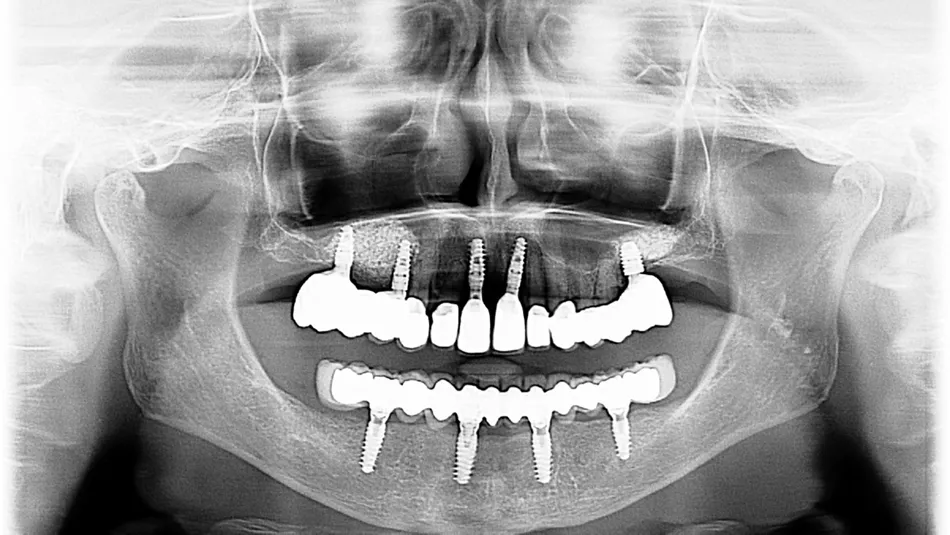

12.  The postoperative OPG shows the implant placement as planned

17.  Final control OPG with the complete treatment of the upper and lower jaw.